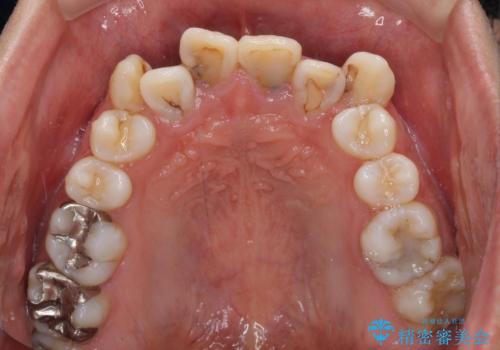

- 八重歯と上顎前歯の変色を気にして来院された患者様です。

上下ともに八重歯が顕著であったため、上下左右の第一小臼歯4本を抜歯し、ワイヤー装置での抜歯矯正を行うこととしました。

前歯は根管治療が必要な歯を事前に根管治療を行い、矯正治療後にオールセラミッククラウンにて補綴治療を行うこととしました。